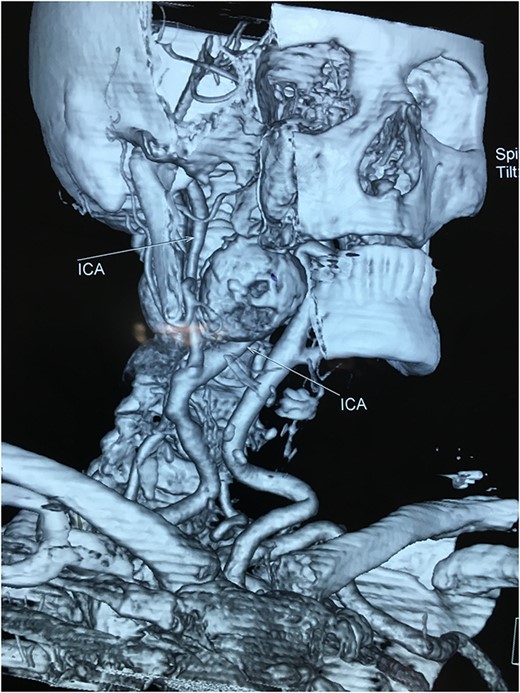

A 71-year-old woman was referred to the vascular surgery department of our hospital with an asymptomatic, pulsative, submandibular mass that she had noticed in the right side of her neck for a month and with ‘potato voice’. Her medical history was non-contributory. MRI, 3D-CT (Fig. 1) and conventional angiography (Fig. 2) revealed an aneurysm of the right ICA. The aneurysm was located in the upper third of the artery and its maximal diameter was more than 4 cm, lining to the right parapharyngeal space, whereas the aerodigestive track was limited and dislocated in the height of the aneurysm.

Computed tomography angiography of the carotids with 3D reconstruction.